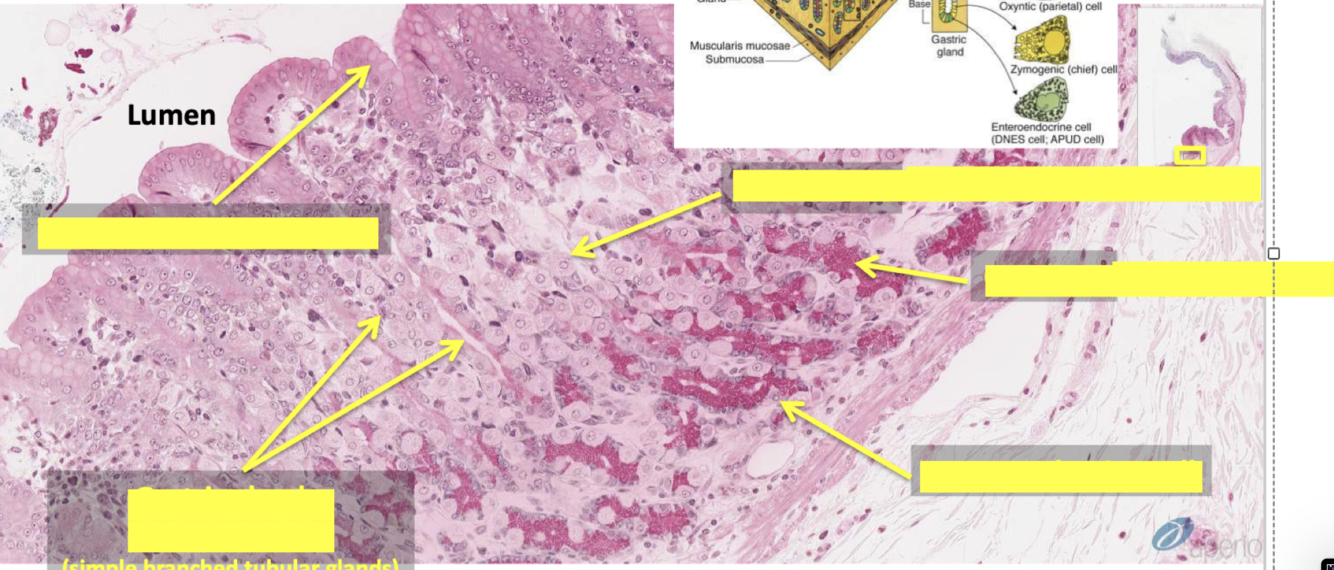

mucosa composed of

muscularis mucosae

what is lamina propria

what is muscularis mucosae

stomach

function of parietal cell

function of chief cell